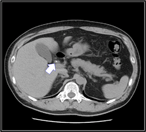

Synchronous contralateral adrenal metastasis of colorectal cancer: case report

Micaela Raices and others

Journal of Surgical Case Reports, Volume 2017, Issue 6, June 2017, rjx098, https://doi.org/10.1093/jscr/rjx098